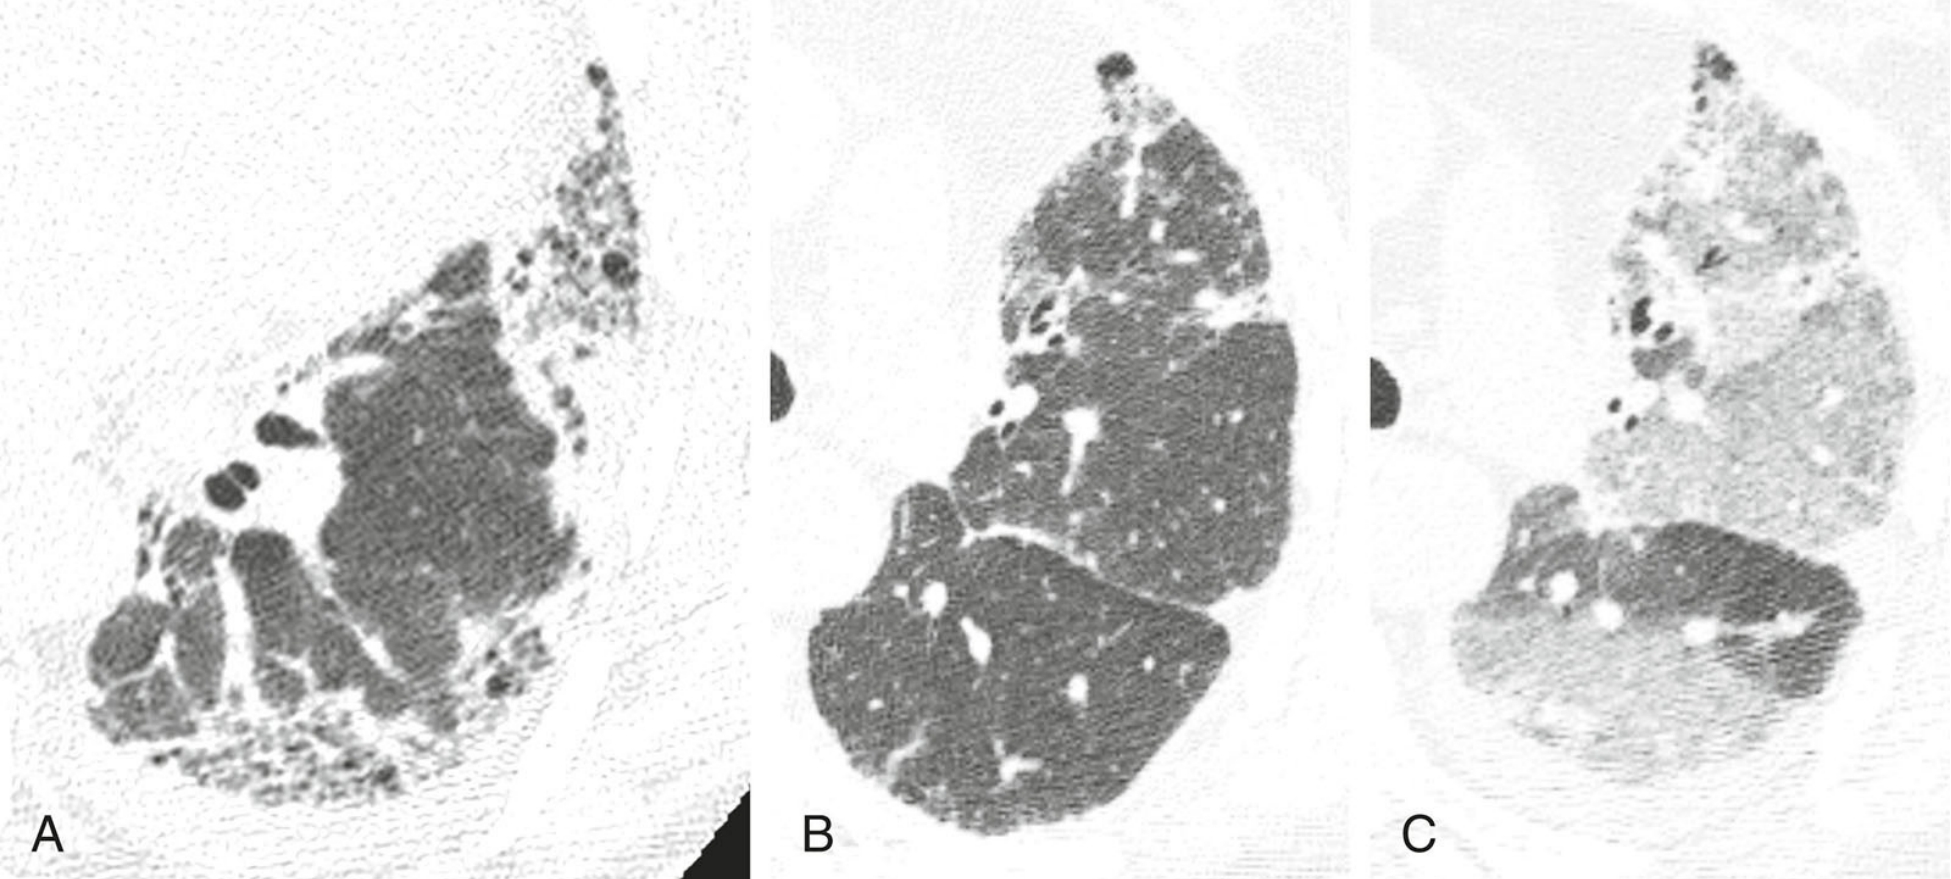

特发性肺间质纤维化(IPF)的典型表现。

上肺(A) 、中肺(B) 、下肺(C)层面的HRCT图像,显示胸膜下和肺基底分布为主的蜂窝征(红箭)和牵拉性支气管扩张(蓝箭),符合普通型间质性肺炎(UIP)。在无已知疾病或接触史的情况下,该患者拟诊为IPF。